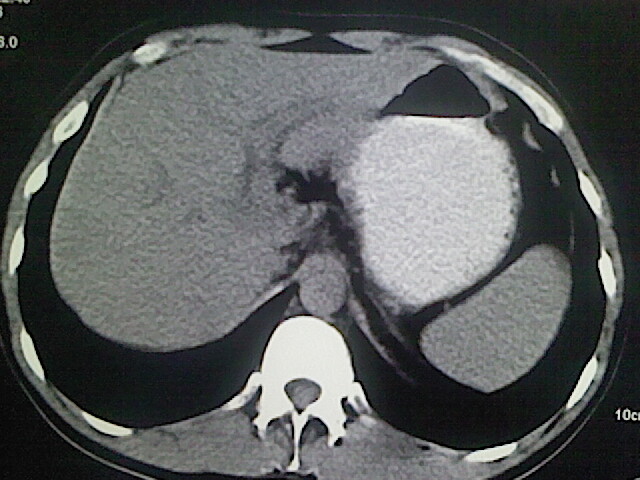

以下是引用卜一在2009-3-14 9:49:00的发言:[br]胆囊萎缩,胆囊壁不规则增厚,内部结构模糊,增强明显强化。另:肝左叶外侧段肝囊肿。支持:慢性胆囊炎!高度可疑:胆囊癌!

以下是引用余辉在2009-3-14 8:48:00的发言:[br]1)慢性胆囊炎。2)肝左叶外侧段肝囊肿。3)脂肪肝。[br]支持,胆囊萎缩,密度增高,不知b超具体有何提示,钙胆汁?结石?

以下是引用jiangjing在2009-3-14 10:18:00的发言:[br]1)慢性胆囊炎。2)肝左叶外侧段肝囊肿。3)脂肪肝。4.】建议行肝功能检查